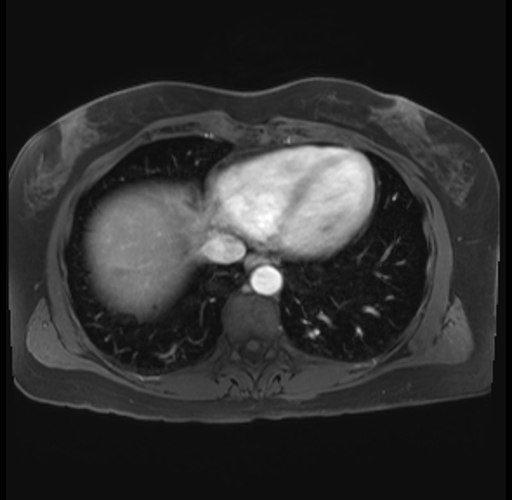

Imaging Analysis

Look through the patient's CT scan to identify any areas of concern for the necessary procedure.

Based on your CT findings, which issue(s) are present and would give reason for "planned slowing down moment(s)" in this case?